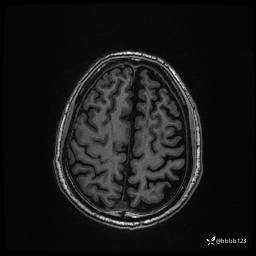

患者男,43岁。

简要病史:癫痫患者复诊,昨日发作5-6次,建议住院进一步治疗。

入院完善脑癫痫组合序列:

3d T1: